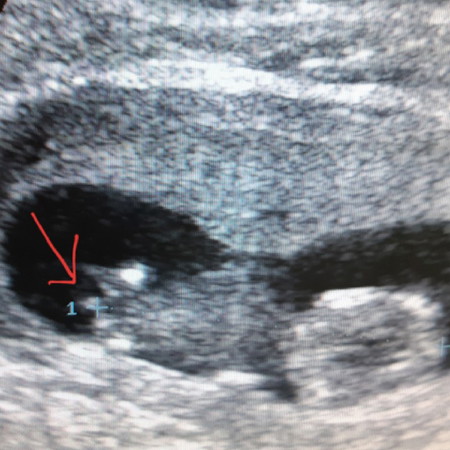

ช่วยดูหน่อย ใช่ปิกก้าจู๋ น้องมั้ย !!! ตอนซาว แค่ 12W1D เอง ในภาพน้องเหมือนน้องจะนอนหันหลังเลย แต่ตรงลูกศร ชี้ เหมือนปิกก้าจู๋จิงๆนะ หรือเราคิดไปเอง...

ปิกก้าจู๋ค่ะ555